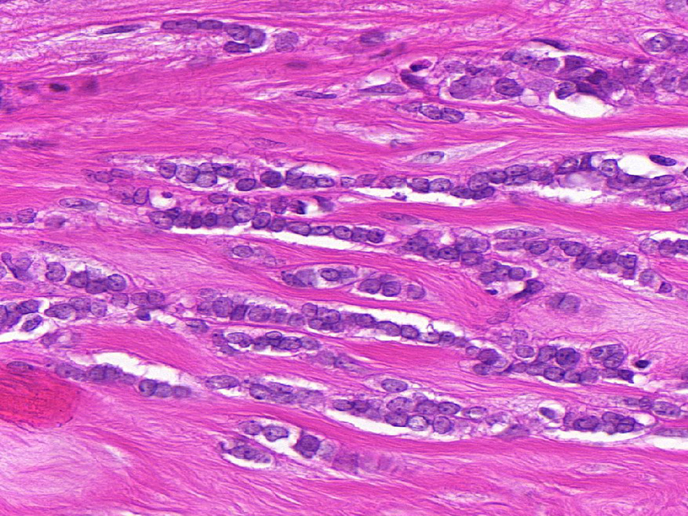

Le génotypage du cancer a corrélé les réponses aux médicaments anticancéreux ciblés avec des mutations de gènes spécifiques. Nombre de ces mutations se produisent dans des composants de signalisation appelés kinases. Les sous-types difficiles à traiter du carcinome lobulaire invasif (CLI) ou du cancer du sein triple négatif (TN), qui représentent 25 % de tous les cancers du sein, manquent actuellement de traitements ciblés, conduisant à un mauvais pronostic de la patiente. Le projet RATHER (Rational Therapy for Breast Cancer: Individualized Treatment for Difficult-to-Treat Breast Cancer Subtypes), financé par l’UE, a élaboré des signatures de biomarqueurs spécifiques permettant de prédire avec précision le résultat chez les patientes présentant un CLI (avec le test MammaPrint) ou la réponse au traitement d’une patiente atteinte d’un cancer du sein TN (avec le test BRCAness), ainsi que de nouveaux traitements non couverts pour les sous-types de cancer du sein. Le potentiel clinique des résultats de RATHER est immédiat pour étendre la portée de MammaPrint (un test de diagnostic déjà approuvé) dans le sous-groupe des cancers du sein CLI. Le projet a également contribué à plusieurs essais cliniques, les travaux produisant de nouvelles approches diagnostiques et thérapeutiques, et ouvrant la voie à des avancées dans le traitement du cancer du sein. Adapter le médicament De nombreux cancers modifient les protéines cellulaires clés appelées kinases. En plus de jouer un rôle clé dans les voies physiologiques, les kinases agissent comme des commutateurs moléculaires contrôlant la croissance et la propagation du cancer. RATHER a étudié les gènes à l’origine des protéines kinases pour déterminer si des modifications spécifiques du code génétique, ou d’autres modifications des cellules cancéreuses d’une patiente, peuvent expliquer la formation et la propagation du cancer. RATHER a examiné le taux d’activation des kinases (le «kinome») dans les tumeurs du sein TN dépourvues de récepteurs œstrogènes, de progestérone et HER2 (15 % des cancers du sein) et de CLI du sein (10 % des tumeurs du sein). Plus particulièrement, 518 gènes de kinases ont été séquencés pour identifier des mutations associées à l’un ou l’autre de ces cancers du sein. En plus du séquençage de l’ADN, les altérations des kinases ont également été évaluées au niveau des ARNm et des protéines afin notamment de démontrer la variation du nombre de copies. Les modifications ont été examinées par des systèmes informatiques et via des modèles laboratoires précliniques. Le professeur William Gallagher, coordinateur du projet, explique: «Notre travail a identifié des différences dans les cancers du sein de différents sous-types et est basé sur le fait que certaines de ces altérations auront des implications dans le développement de la maladie, au delà de simples effets aléatoires». Lorsque cela était possible, les inhibiteurs de petites molécules ont été sélectionnés en fonction de leur capacité à limiter la croissance des cellules exprimant des altérations de kinases spécifiques à un sous-type. Le consortium RATHER a joué un rôle de premier plan dans un essai clinique multicentrique de phase Ib/II portant sur un nouveau médicament inhibiteur de la kinase appelé «taselisib». L’essai initial de phase Ib a montré avec succès qu’une combinaison d’un traitement endocrinien traditionnel (le médicament tamoxifène) et de ce nouvel inhibiteur de kinase était bien tolérée par les patientes. Comme le résume le professeur Gallagher, «en découvrant les modifications apportées à des kinases particulières et à la fonction de la protéine mutée, puis en remontant au sous-type spécifique du cancer du sein de la patiente, nous avons découvert plusieurs nouvelles façons de prédire avec précision les résultats pour les patientes et potentiellement de traiter plus efficacement les patientes présentant ce sous-type». RATHER contribue directement aux applications qui fourniront non seulement des diagnostics améliorés, mais également des options thérapeutiques pour le cancer du sein, l’une des principales causes de décès liés au cancer chez les femmes. Le travail de RATHER s’aligne sur les efforts plus larges visant à un traitement plus individualisé du cancer. L’essai clinique de phase II du nouvel inhibiteur de kinase est actuellement en cours parallèlement à des essais complémentaires.